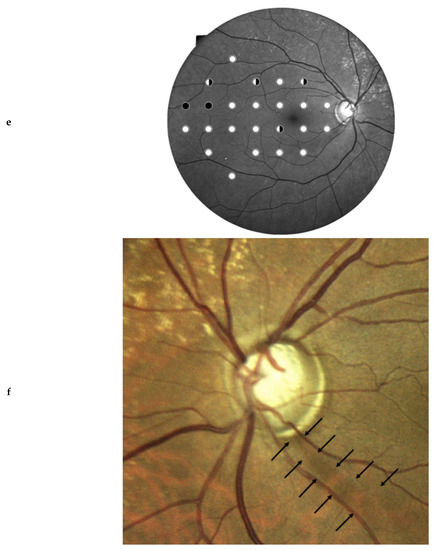

Figure 2 shows the examinations of a patient with glaucoma showing agreement between clinical diagnosis and SST on right eye, and disagreement between clinical diagnosis and QST on left eye.

On the other hand, CMP has the strong advantage of allowing a direct integration between morphology and function by directly inspecting on the same printout a red-free image and a color image of the central retina including the optic nerve head and the perimetric results [18]. Integration of morphology and function increases the diagnostic accuracy of glaucoma diagnosis, both at screening [7] and non-screening levels [17]. This topic could not be formally tested, as there were few cases with incoherent results between clinics and screening tests due to the small cohort of subjects included. Confirmation by large population studies is warranted. Still, the case described in Figure 2 clearly highlights the advantage of adding structural information to the decisional process.

Figure 2. This is the case of a 60-year-old woman with bilateral glaucoma. Standard perimetry showed a bilateral damage (a) Right eye, superior relative diffuse defect; (b) Left eye, relative superior nasal step and relative inferior arcuate defect). (c) OCT showed focal RNFL thinning corresponding to the visual field damage in both eyes. (d) The patient received SST in the right eye, and defects at both hemifields were correctly identified; the test was deemed as abnormal (STR = 2%), in agreement with the clinical judgement. (e) In the left eye, the patient underwent QST. The screening procedure was able to detect the damage in the superior hemifield shown with standard perimetry; in the inferior hemifield, just an abnormal nasal location was correctly identified, whereas the peripheral abnormal locations of the standard perimetry were undetected. The judgement by STR was borderline (8%). Interestingly, the presence of ONH imaging would strongly allow direct integration of functional and morphological data. (f) Inspecting the glaucomatous optic nerve head with RNFL defects (arrows), an ophthalmologist would easily perform a correct assessment of glaucoma.